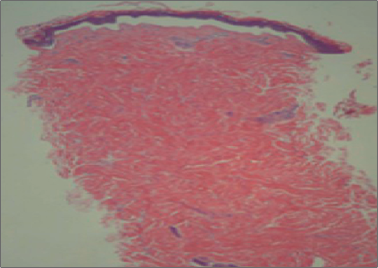

在100名使用黃金微針射頻實驗者中隨機(jī)抽取,在治療后即日、2天、7天、14天、28天和70天后,采用切片檢查法,觀察皮膚的變化,結(jié)果證實膠原蛋白等細(xì)胞因子均有50%~400%的增長。一次治療,即可明顯緊致肌膚、亮膚美白、縮小毛孔。